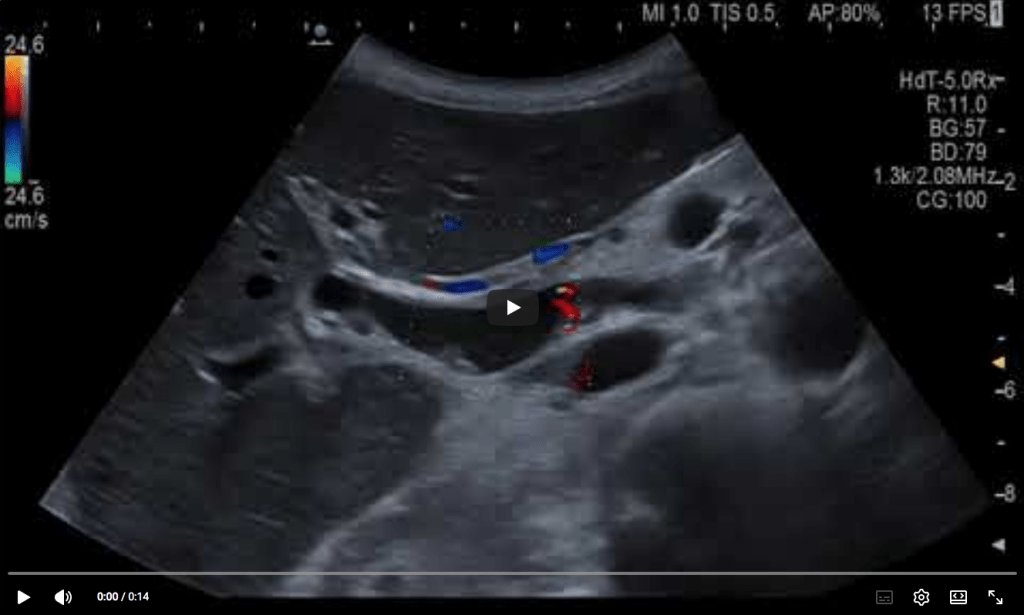

Endorectal ultrasound (ERUS) performed with a linear flexible EUS scope shows a well-defined, circumscribed, collection filled with mixed hypoechoic and hyperechoic content (Image 1 + 2). Intravenous CEUS (4.8 mL) depicted uptake of the ultrasound contrast agent inside various septations and granulation tissue in the collection (Video 1). Transrectal injection of diluted Sonovue (0.2 mL in 10 mL of saline) depicted the extent of the pararectal collection which communicated with a cranial and caudal fistula (Video 2). The EUS-guided aspirate yielded pus, with later growth of Enterobacter + anaerobe species. Last but not least, perineal CEUS examination with a convex probe showed the horseshoe abscess surrounding the rectum (Video 3).